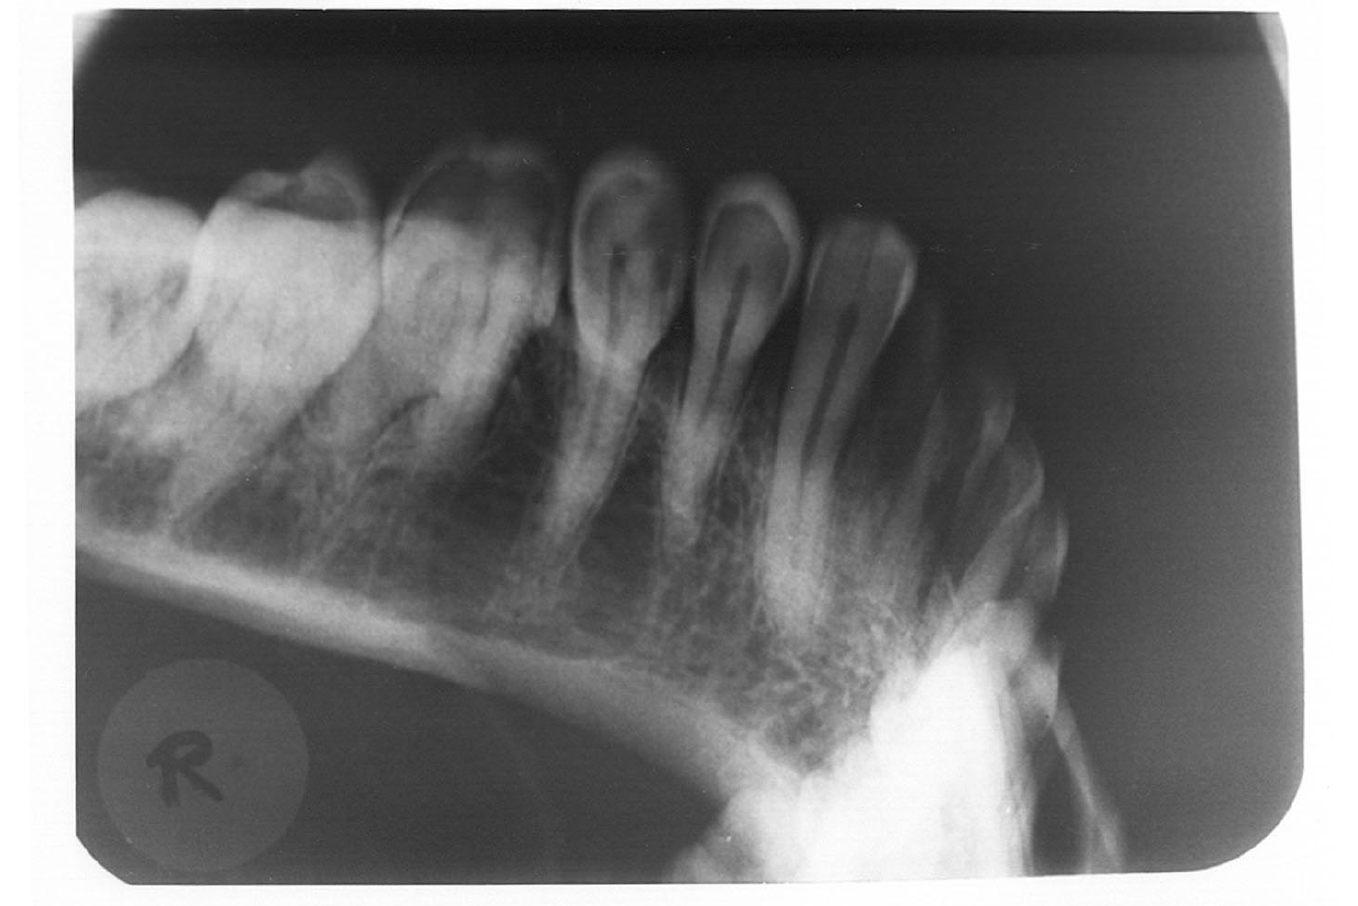

The purpose of the intraoral periapical examination is to obtain a view of the entire tooth and its surrounding structures, as in Figure 1. Two exposure techniques may be employed for periapical radiography: the paralleling technique and the bisecting angle technique. The paralleling technique is the preferred method. This technique provides less image distortion and reduces excess radiation to the patient. The paralleling technique should always be attempted before other techniques. The bisecting technique can be employed for patients unable to accommodate the positioning of the paralleling technique. Candidates may include those with low palatal vaults and children. Disadvantages to the bisecting technique include image distortion and excess radiation due to increased angulations involving the eye and thyroid glands. Regardless of the technique, however, the rules of radiography referred to earlier must be followed.

Figure 1 - Periapical Image

Figure 1